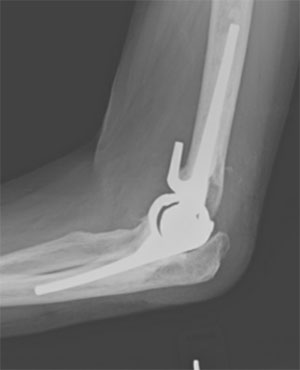

- Elbow arthritis (osteoarthritis)

- Post-traumatic arthritis